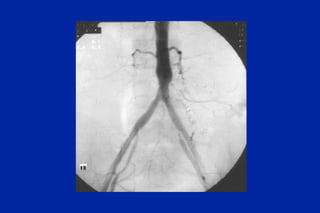

Este documento resume los principales tipos y técnicas de angiografía. Describe brevemente la angiografía, arteriografía, flebografía y linfografía, así como las técnicas de contraste y materiales utilizados. También explica los principales accesos vasculares, la técnica de Seldinger, la angiografía por sustracción digital y algunas técnicas endovasculares comunes.